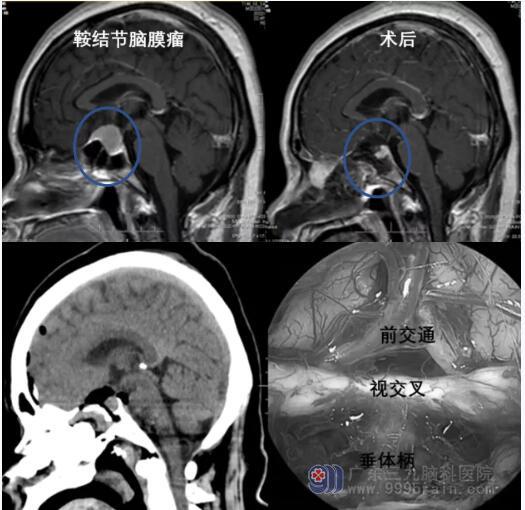

颅底中线的脑膜瘤

脑膜瘤是常见的原发性颅内病变。神经内镜辅助经鼻切除术已成为颅底中线脑膜瘤首选治疗方法,适合运用于治疗发生在前颅窝的中小型脑膜瘤,如蝶骨平台和鞍结节脑膜瘤和斜坡脑膜瘤等。神经内镜经鼻手术可减少脑损伤,患者术后颅神经的并发症和术后住院时间等均可得到改善。如果肿瘤压迫视神经导致视力受损时,神经内镜经鼻入路还能对视神经管进行早期减压,早期挽救视力。